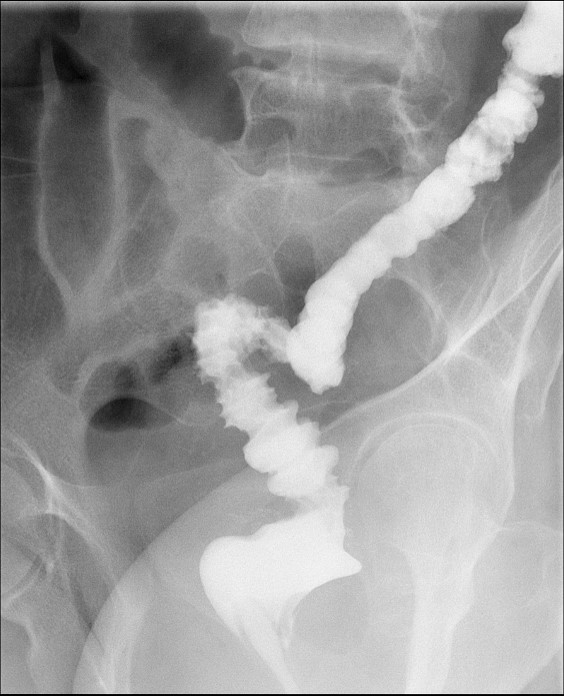

- Obtain images of the terminal ileum and the ileocecal valve filled with contrast material

(key image 6)

(key image 7)

(key image 8)

(key image 9)

(key image 10).

- Obtain spot images of the remainder of the small bowel

(key image 11)

(key image 12)

(key image 13)

(key image 14).

- Obtain images of all four quadrants. Use the compression paddle to separate loops of small bowel from each other.